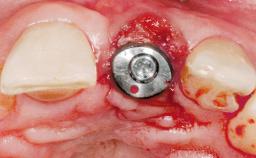

Immediate Flapless Placement of an Implant in a Maxillary Right Lateral Incisor Site

This 43-year-old male patient, a non-smoker, came to our practice because of a fracture of tooth 12 caused by a bicycle accident. Due to the combined para- and infrabony crown and root fracture, tooth extraction, and subsequent implant placement were suggested to the patient as the therapy of choice. The patient had high esthetic expectations with regard to the treatment outcome and asked for an immediate fixed provisional restoration. His individual esthetic risk profile summed up to a medium esthetic risk.

Loading Protocol Immediate

Retention Screw-retained Screw-retained

Provisional Implant-Supported Prosthesis Prosthodontic margin > 3 mm apical to mucosal margin Prosthodontic margin > 3 mm apical to mucosal margin